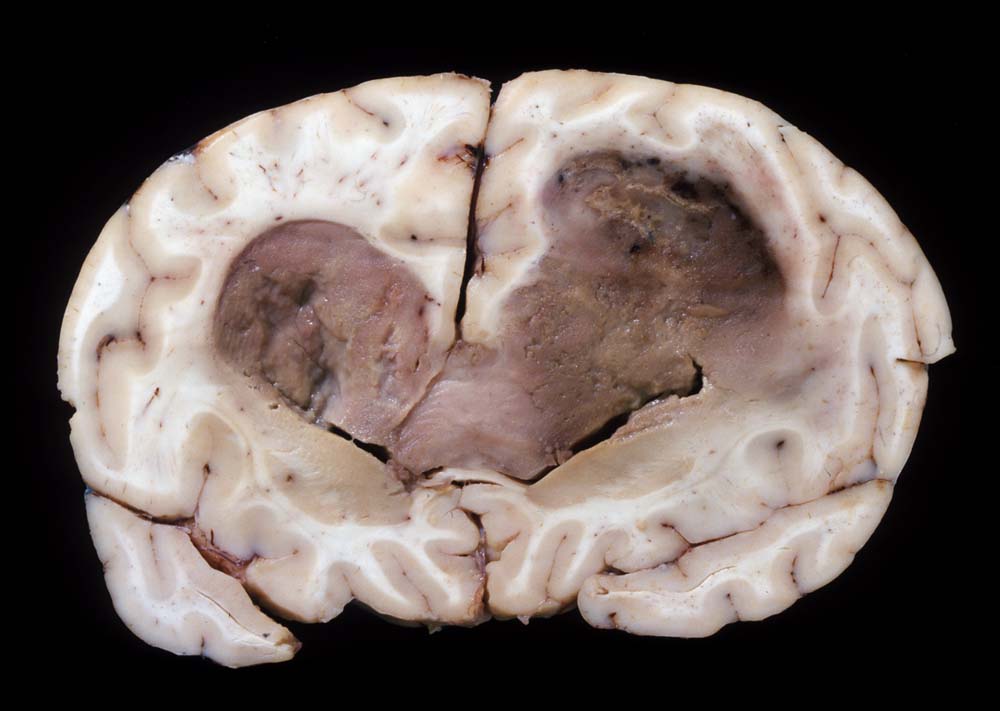

Glioblastoma multiforme

Beginnend im Marklager des rechten Frontallappens, findet sich eine zystische bräunliche Raumforderung mit perifokalem Ödem, welche sich in dorsaler Richtung den Balken infiltrierend in das Marklager der linken Hemisphäre ausdehnt. Die Raumforderung ist von weicher Konsistenz mit teils nekrotischen Arealen und von graubrauner, teilweise auch gelblicher Farbe. Sie dehnt sich in beiden Hemisphären aus, wächst in die Seitenventrikel ein und füllt diese zum Teil komplett aus. Hirnödem mit verbreiteten Gyri.

Seit zwei Monaten frontale Kopfschmerzen. CT- und MRI-Untersuchungen zeigten eine bifrontale interkranielle Raumforderung. Bioptische Diagnose eines Glioblastoma multiforme.